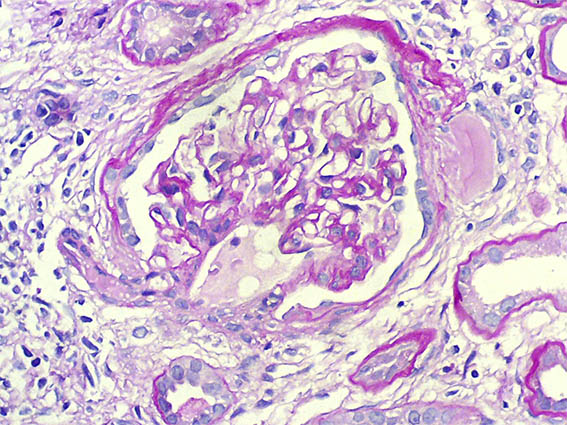

Figura 9.

Tricrómico de Masson, X400.

Figura 10. Plata-metenamina, X400.